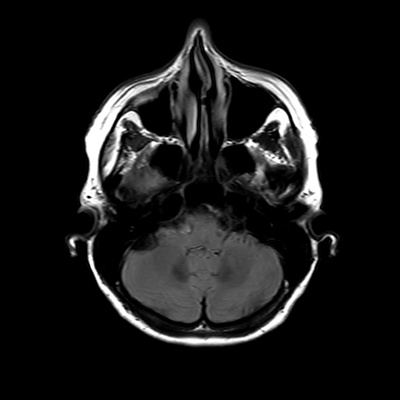

You also obtain an MRI of his brain once it's clinically safe to do so.

MRI brain (FLAIR)